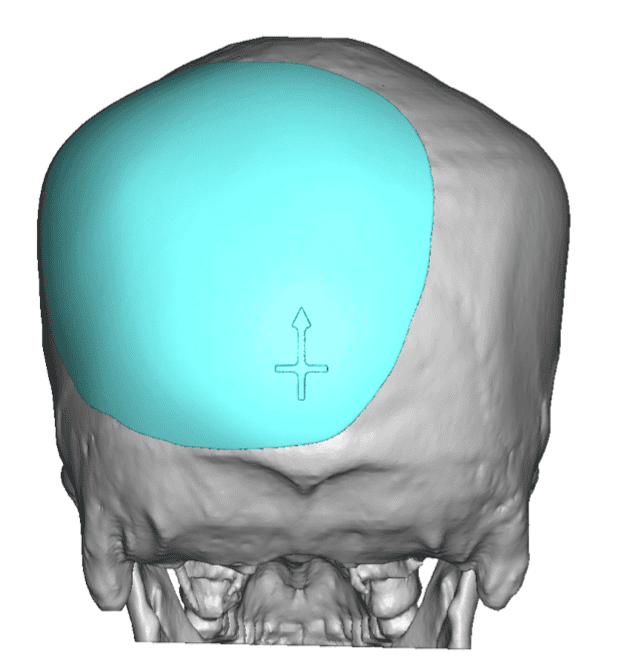

Patient 51

Desire for taller and rounder head shape.

Two stage custom skull implant augmentation technique.

Desire for taller and rounder head shape.

Two stage custom skull implant augmentation technique.